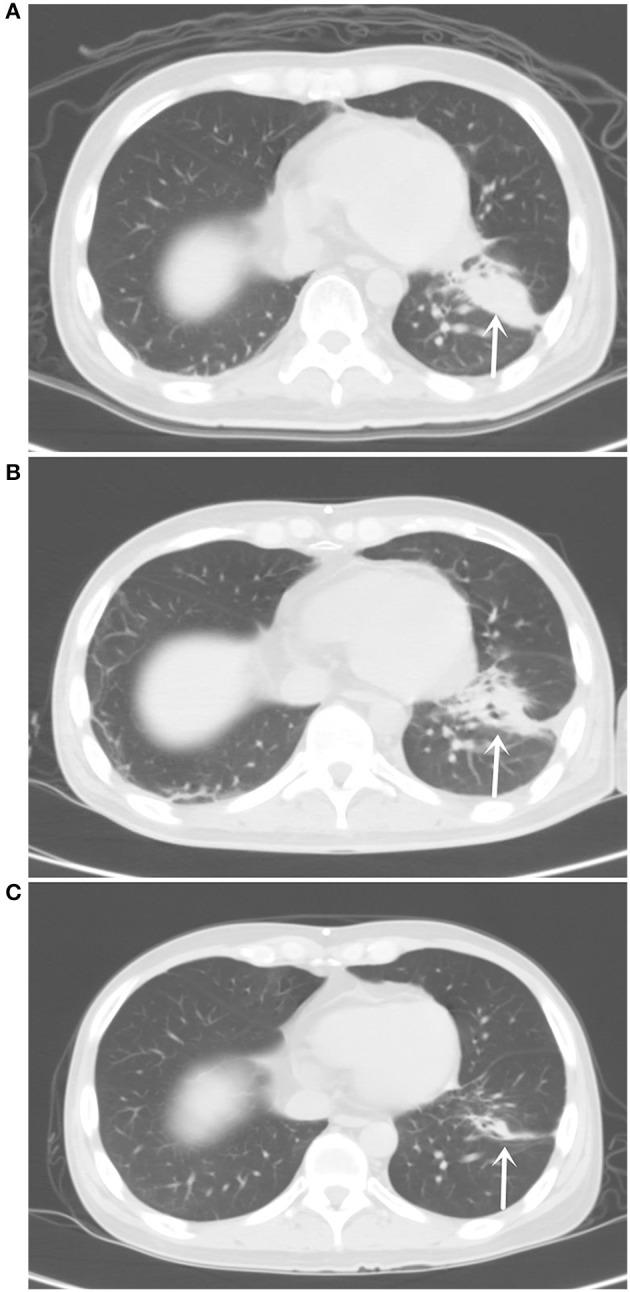

In patients with lung adenocarcinoma and leptomeningeal metastases, it remains unknown whether non-classical mutations in the epidermal growth factor receptor (EGFR) gene can be detected in the cerebrospinal fluid (CSF) and how it may be used to design directed therapy. On April 18, 2018, the Interventional Department of Tianjin Huanhu Hospital admitted a 34-years-old male patient with lung adenocarcinoma and leptomeningeal metastasis. An emergency lateral ventriculoperitoneal shunt was performed to relieve the clinical symptoms of intracranial hypertension. Next-generation sequencing (NGS) of the CFS specimens revealed a mutation in EGFR exon 18 p.G719A, and afatinib was administered. Follow-up showed significantly relieved headache, with significantly reduced soft leptomeningeal abnormal enhancement as revealed by enhanced magnetic resonance imaging and significantly smaller tumors in the left lung by chest computed tomography. Carcinoembryonic antigens (CEAs) in cerebrospinal fluid and peripheral blood were significantly reduced. The patient responded well to afatinib, with mild adverse complications. The patient died on October 27, 2019 from respiratory failure as a result of lung infection unrelated to cancer progression. The overall survival (OS) using afatinib was 530 days. CSF can be used as a liquid biopsy for NGS gene detection in patients with lung adenocarcinoma and leptomeningeal metastases. Afatinib exhibits a beneficial effect in patients with lung adenocarcinoma and leptomeningeal metastases harboring the EGFR exon 18 p.G719A mutation.

在肺腺癌合并软脑膜转移的患者中,目前尚不清楚脑脊液(CSF)中是否能检测到表皮生长因子受体(EGFR)基因的非经典突变,以及如何利用这些突变来设计靶向治疗方案。2018年4月18日,天津环湖医院介入科收治了一名34岁的男性肺腺癌合并软脑膜转移患者。紧急进行了侧脑室腹腔分流术以缓解颅内高压的临床症状。对脑脊液标本进行二代测序(NGS)发现EGFR基因第18外显子存在p.G719A突变,随后给予阿法替尼治疗。随访结果显示,患者头痛明显缓解,增强磁共振成像显示软脑膜异常强化明显减轻,胸部计算机断层扫描显示左肺肿瘤明显缩小。脑脊液和外周血中的癌胚抗原(CEA)显著降低。患者对阿法替尼反应良好,出现轻度不良并发症。患者于2019年10月27日因与癌症进展无关的肺部感染导致呼吸衰竭死亡。使用阿法替尼治疗的总生存期(OS)为530天。脑脊液可作为肺腺癌合并软脑膜转移患者进行NGS基因检测的液体活检样本。阿法替尼对携带EGFR基因第18外显子p.G719A突变的肺腺癌合并软脑膜转移患者具有有益疗效。